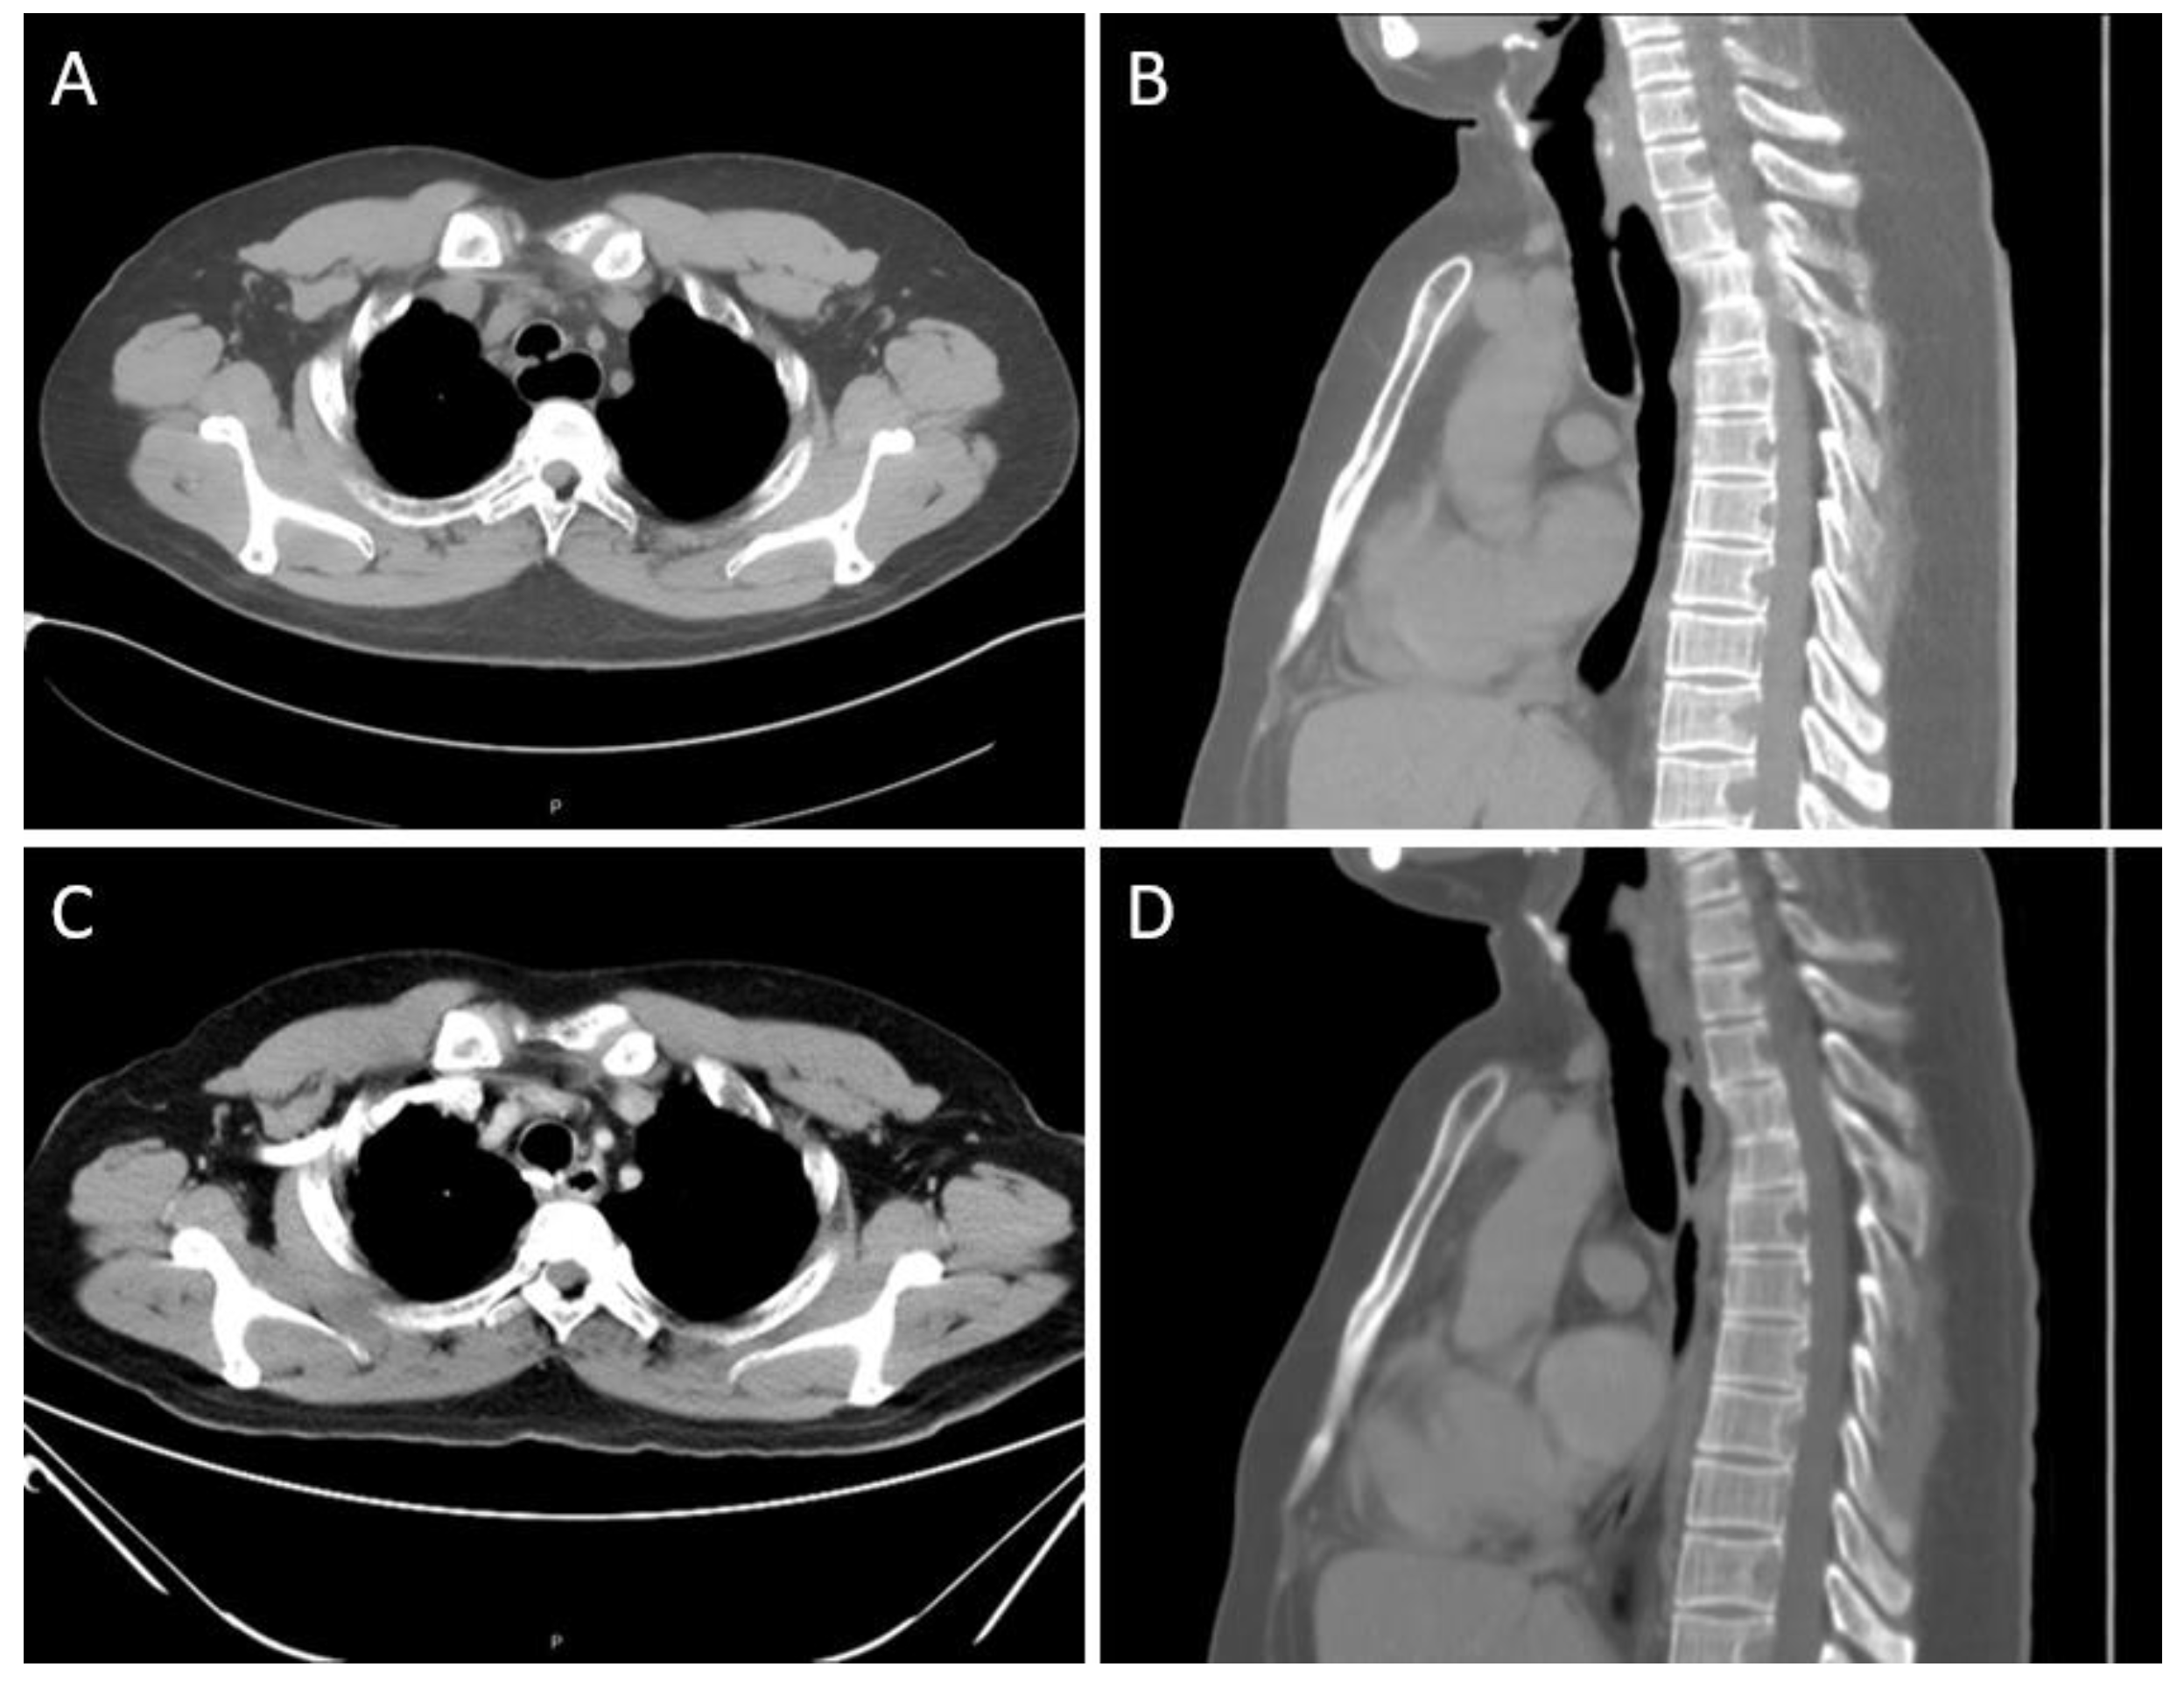

A 31-year-old non-smoker male patient without underlying disease complained of intermittent productive cough since early adulthood, and his cough sometimes worsened after a liquid diet. Other symptoms, including dyspnea, dysphagia, abdominal fullness, and easy chocking, were absent. He also remembered that repeated hospitalizations owing to recurrent bouts of pneumonia had been required. Upon the latest admission for treating pneumonia, a computed tomography (CT) of the chest revealed a small fistula between the trachea and the dilated esophagus at a T2 level (Figure 1A,B); further thin-sliced, three-dimensional (3D) reconstruction scans clearly demonstrated the location of the fistula (Figure 2A,B).

A 24-Fr. chest tube was placed, and the incision wound was closed. On postoperative day 2, the patient resumed oral intake with a soft diet. This was well tolerated without choking for the following days. On postoperative day 5, no overt radiological evidence of contrast leakage nor evident fistula was observed in an esophagogram, and the chest tube was removed. He was discharged uneventfully on postoperative day 7. Six months later, he reported markedly improved symptoms after meals. The follow-up chest CT revealed a normalized esophageal diameter (Figure 1C,D) as well as no evidence of a residual fistula (Figure 2C,D).

Figure 1. Preoperative and postoperative CT scans of the patient. (A) The axial view of pre-op scan showed a fistulous tract between the trachea and the dilated esophagus. (B) The sagittal view of pre-op scan showed the fistula at T2 level. (C) The axial view of the post-op scan six months later demonstrated a normalized esophageal diameter. (D) The sagittal view of the post-op scan showed no evidence of a residual fistula.